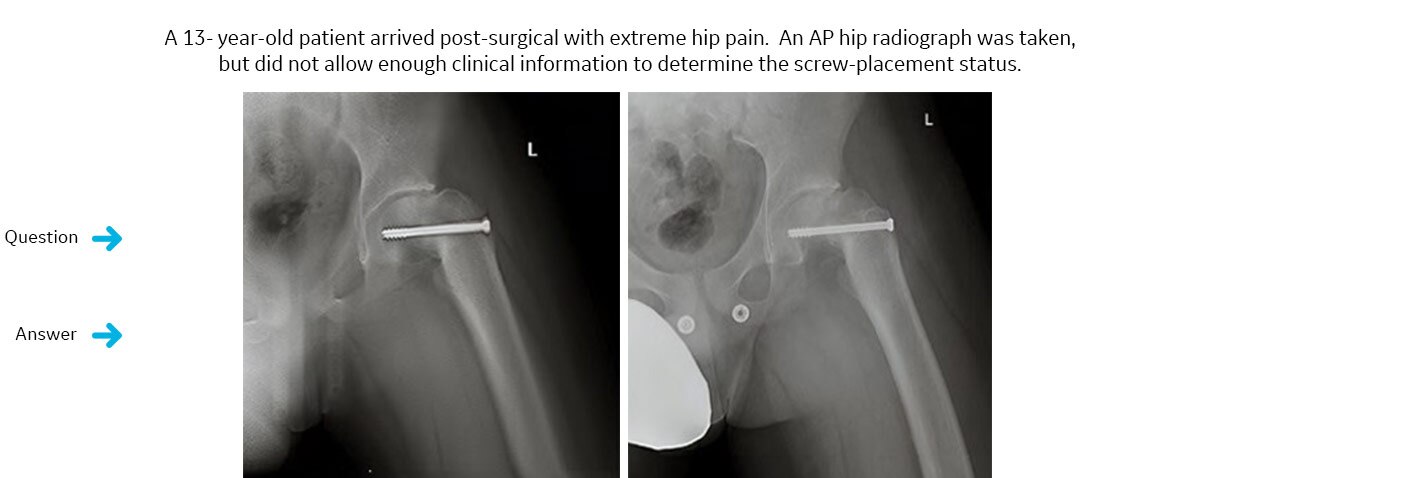

¿Ha invadido el tornillo implantado el espacio de la articulación de la cadera?

Se solicitó un estudio VolumeRAD. VolumeRAD permite la eliminación de estructuras superpuestas y ayuda a realizar un diagnóstico confiable.La respuesta definitiva: no.

Un intervalo de un solo corte de los datos de VolumeRAD reveló que el tornillo implantado no había invadido el espacio articular. El paciente se sometió a una intervención quirúrgica secundaria y se confirmó la correcta colocación del implante.